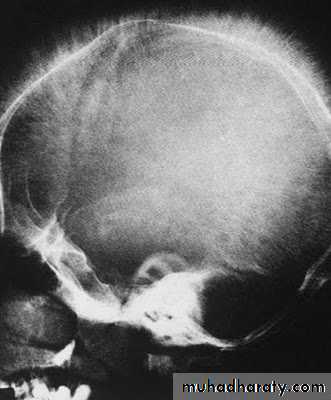

Hyperparathyroidism

Xrays:

sub-periosteal resorptionpepper pot skull

rugger jersey spine

cystic brown tumours